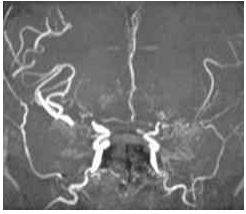

47 35 歲健康女性,早上起床時,突然發生失語症,右側肢體無力,經腦部核磁共振掃描檢查結果如下 圖,其最可能的診斷為何? (A)Fabry disease (B)可逆性後側腦白質病變症候群(reversible posterior leukoencephalopathy syndrome) (C)粒線體病變 (D)moyamoya 症

48 66 歲男性,已知高血壓多年但未控制,突發頭痛、意識不清與癲癇,至急診時血壓為 240/130 mmHg, 神經學檢查意識混沌,但無局部肢體無力現象,腦部磁振照影檢查最可能的發現為何? (A)小腦(cerebellum)出血 (B)視丘(thalamus)出血 (C)大腦枕葉部(occipital lobe)水腫 (D)中腦(midbrain)梗塞